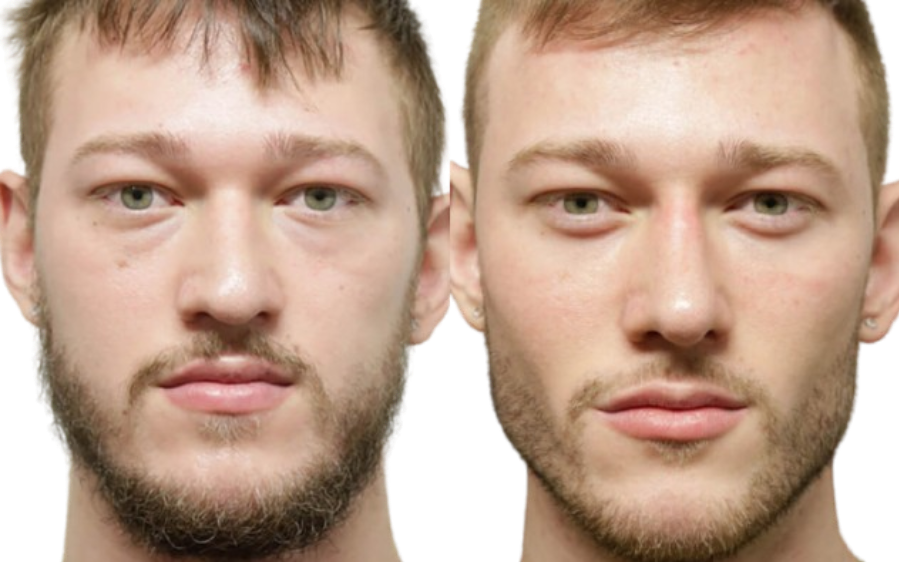

GENIOPLASTY & CHIN SURGERY

Sliding Genioplasty, Chin Implants, Chin Wing

FACIAL IMPLANTS

Jaw Angle · Wraparound Jaw · Zygomatic/Malar · Infraorbital Rim · Supraorbital/Brow · Custom PEEK/Silicone